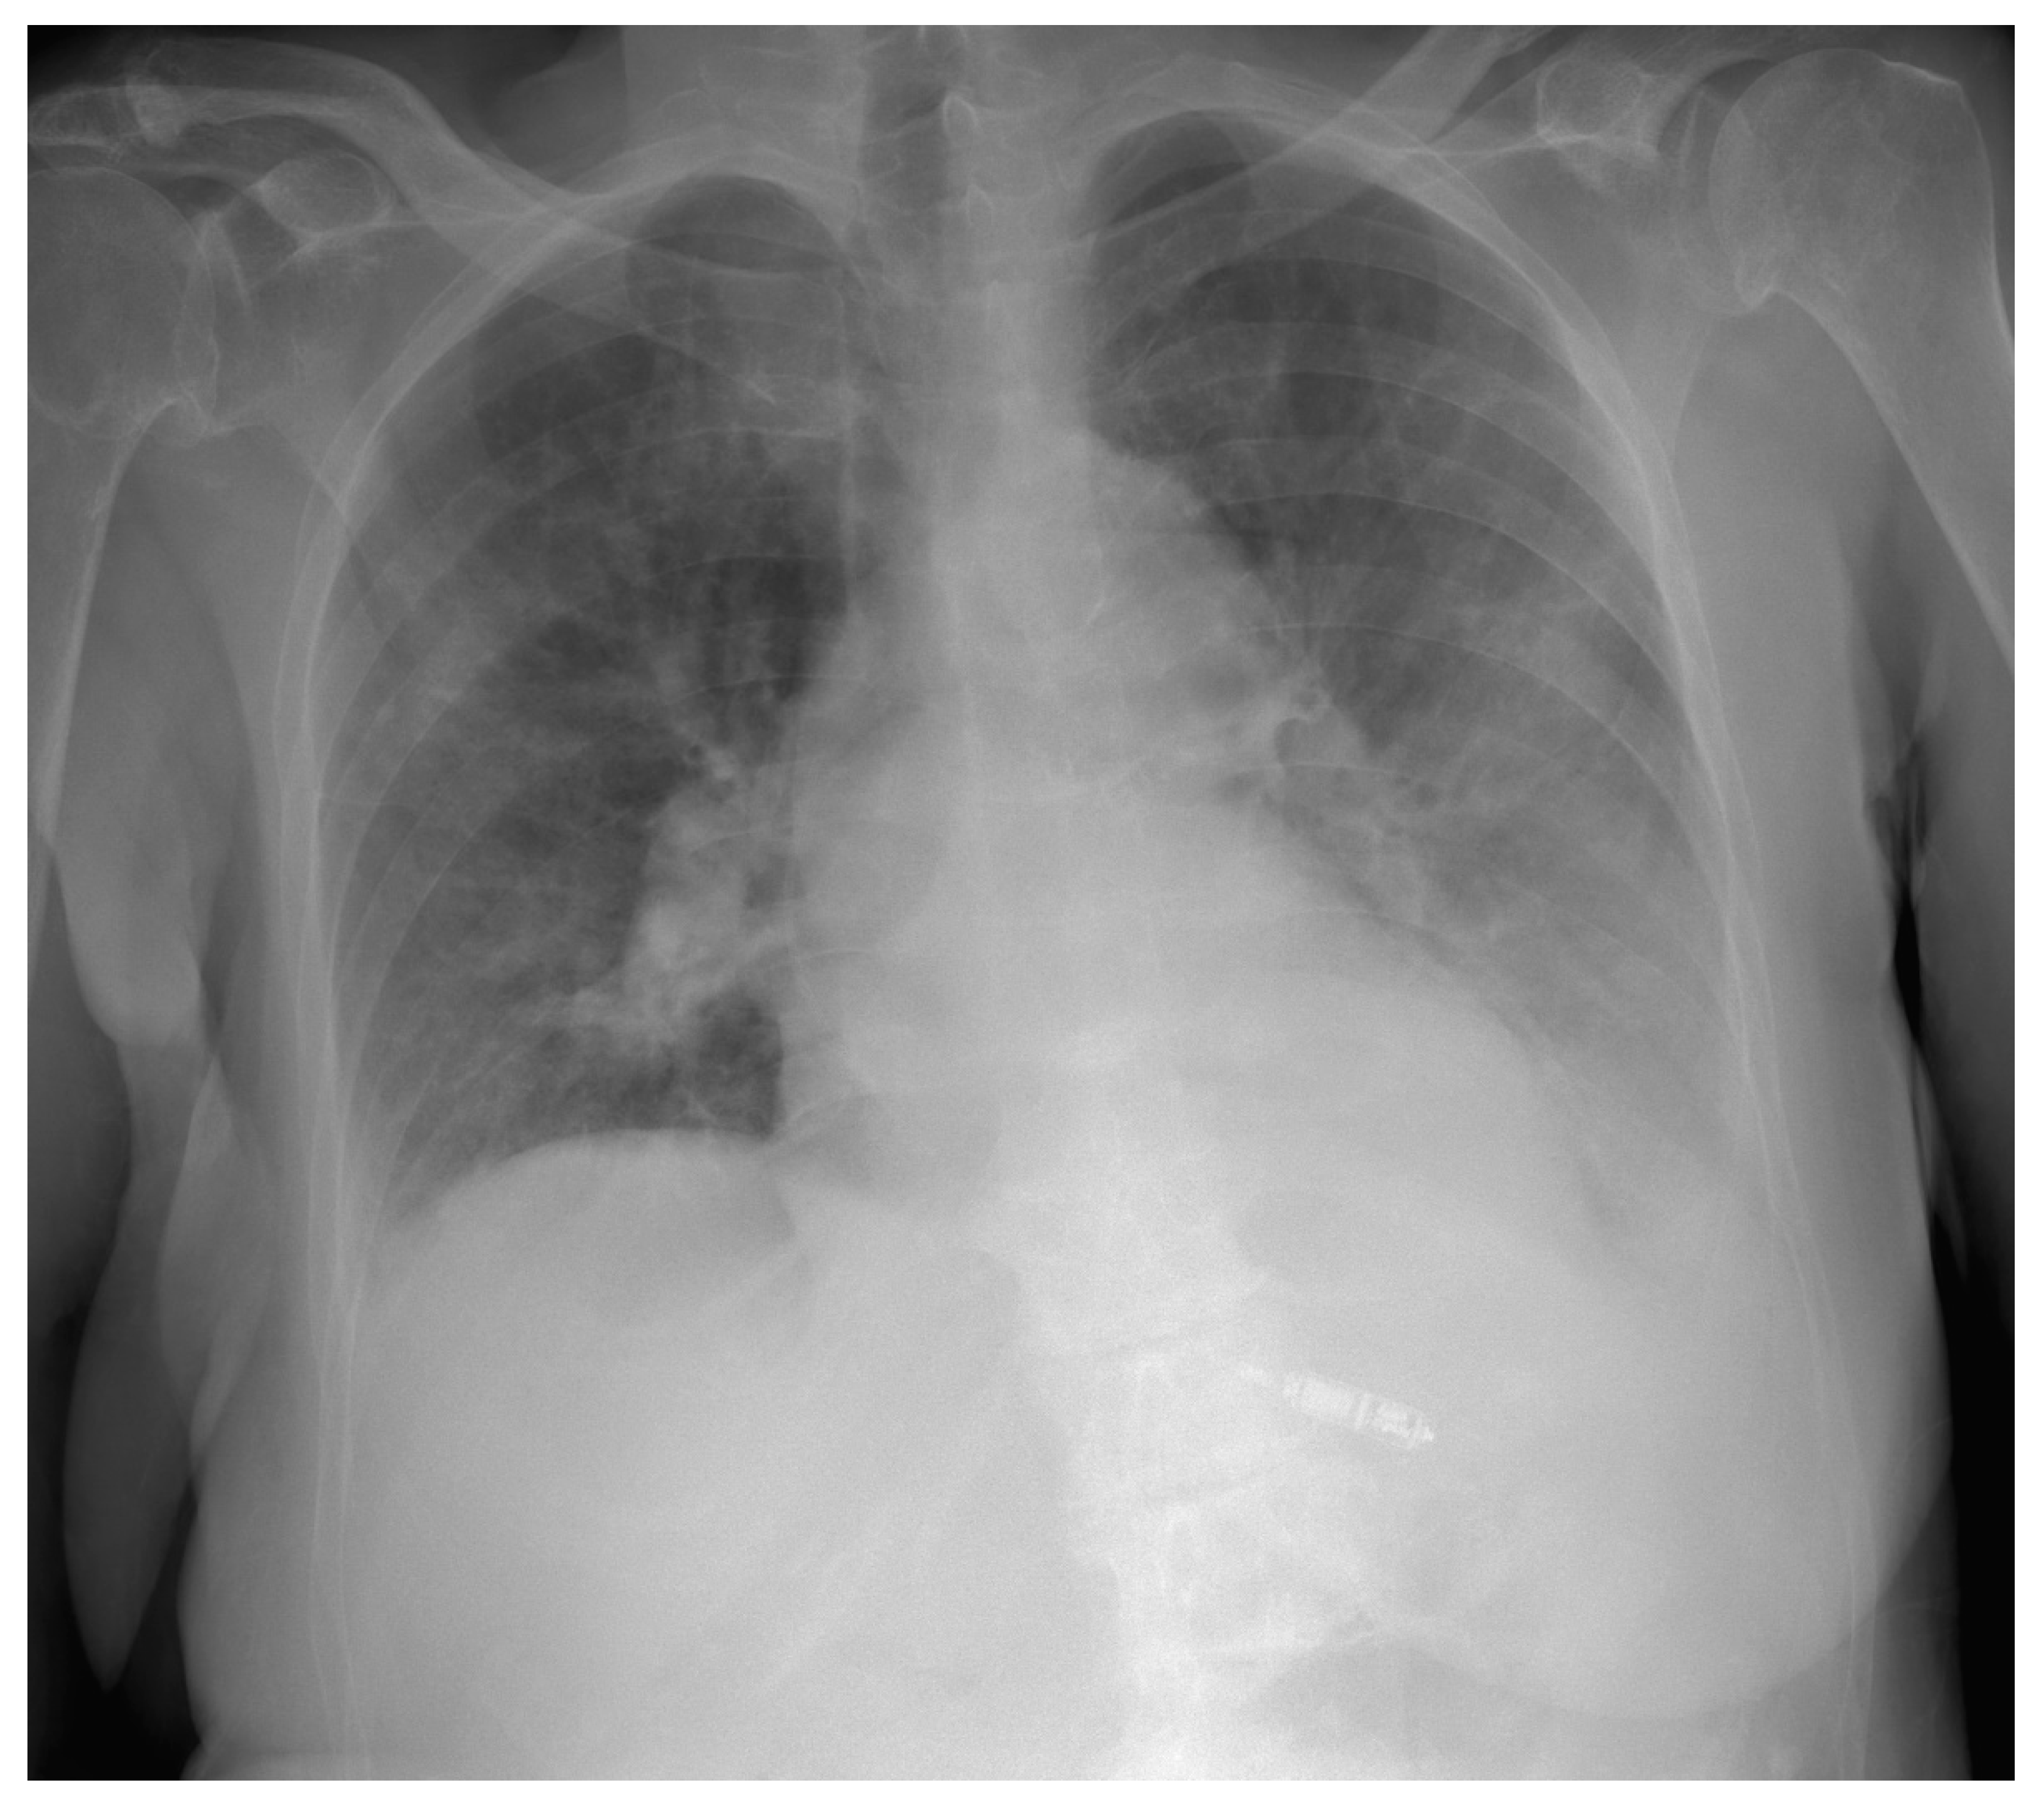

2. Case Presentation